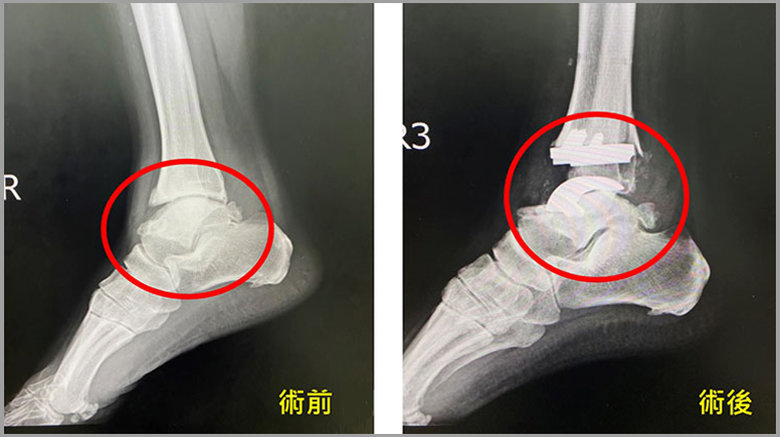

腳踝受傷長期不治療 醫師檢查時軟骨已經磨損光光

楊志鴻表示,病患從事農務工作,檢查發查原先為右腳踝距骨小骨折,因為當時沒有治療,這十幾年來持續的勞動下,右腳踝關節最終引發為外傷性關節炎,裡面的軟骨全部都磨損掉了,右腳不太能夠負重,造成走路都是一跛一跛的,在工作上或日常生活上都非常的不便。

楊志鴻說,外傷性踝關節的治療方式多是以關節融合的方式做關節固定術,但缺點為把關節做死,雖然術後可正常行走,但活動易受限,不符合翁女士的需求,因此建議進行「全踝關節置換術」。手術時將軟骨移除,換上金屬材質的人工踝關節,取代原本關節,因為人工踝關節模仿人體踝關節的構造,能夠保留踝關節80%以上的活動角度,走起路來會比較自然,雖然必需自費,但翁女士覺得這樣的花費是值得的!

楊志鴻指出,若患者希望維持踝關節活動度時,「全踝關節置換術」是治療新選項,國外文獻顯示對合適的病患,緩解疼痛的效果和術後的步態相比術前也有明顯改善。另楊志鴻也提醒,如果因扭傷或跌倒造成踝關節腫脹,要及早來骨科門診照X光檢查骨頭有沒有受傷,若腫脹的程度持續兩個禮拜以上,千萬不能等閒視之。